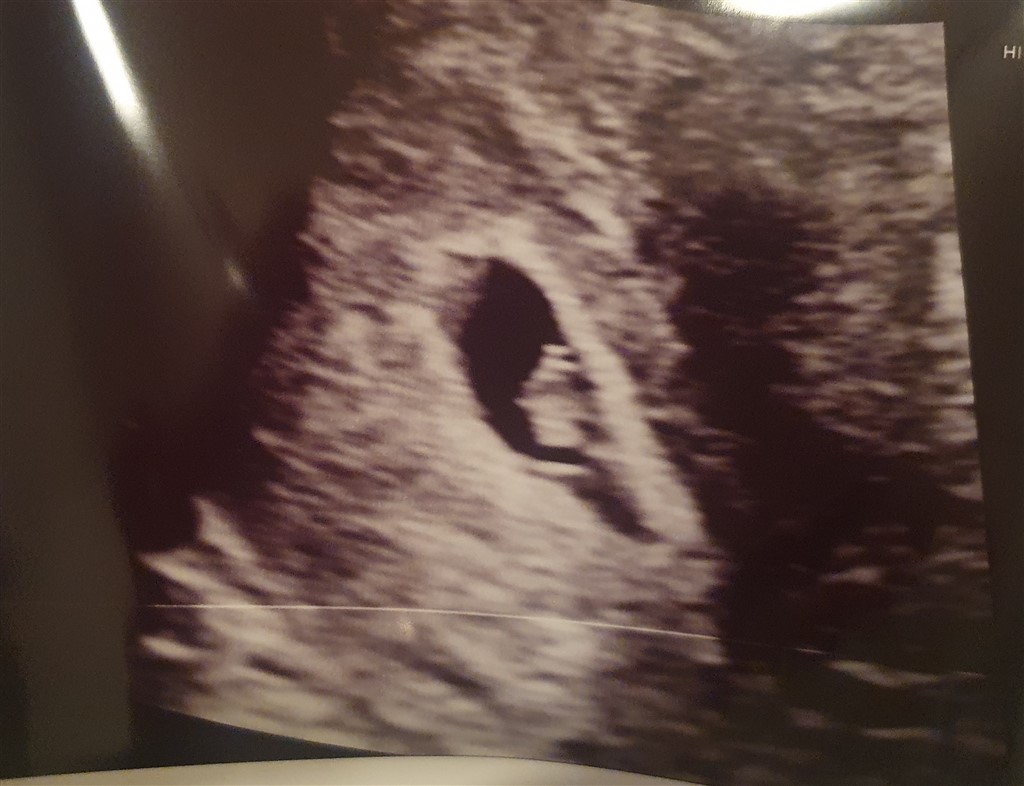

Tror jeg har nogenlunde vænnet mig til tanken, men der er stadig meget der rumsterer. Men det er nu lidt hyggeligt at lave et lille liv igen her er lige et billede fra scanning 7+0

Vedhæftede fotos (klik for at se i fuld størrelse)